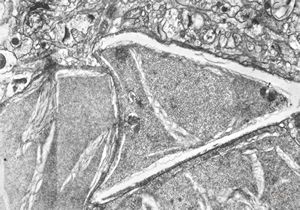

F,50y. | progressive multifocal leukoencephalopathy- viral particles in a glial cell

F,50y. | progressive multifocal leukoencephalopathy- viral particles in a glial cell

F,50y. | progressive multifocal leukoencephalopathy- viral particles in a glial cell